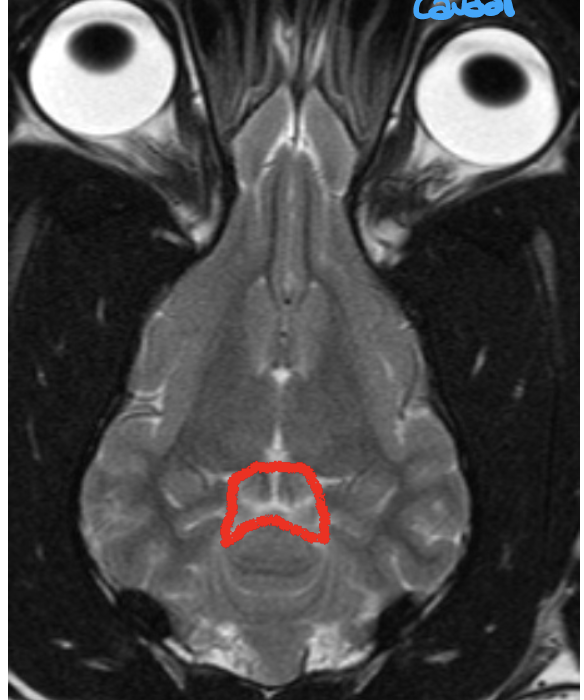

what structure is shown here

diencephalon

what structures are shown here

what does the diencephalon give rise to

the optic nerve

what does the diencephalon contain

third ventricle –> pocket of fluid

what is on the roof of third ventricle

pineal gland is on the dorsal roof of the third ventricle

what can the diencephalon be divided into

four regions

what is on the ventral part of the third ventricle

pituitary gland